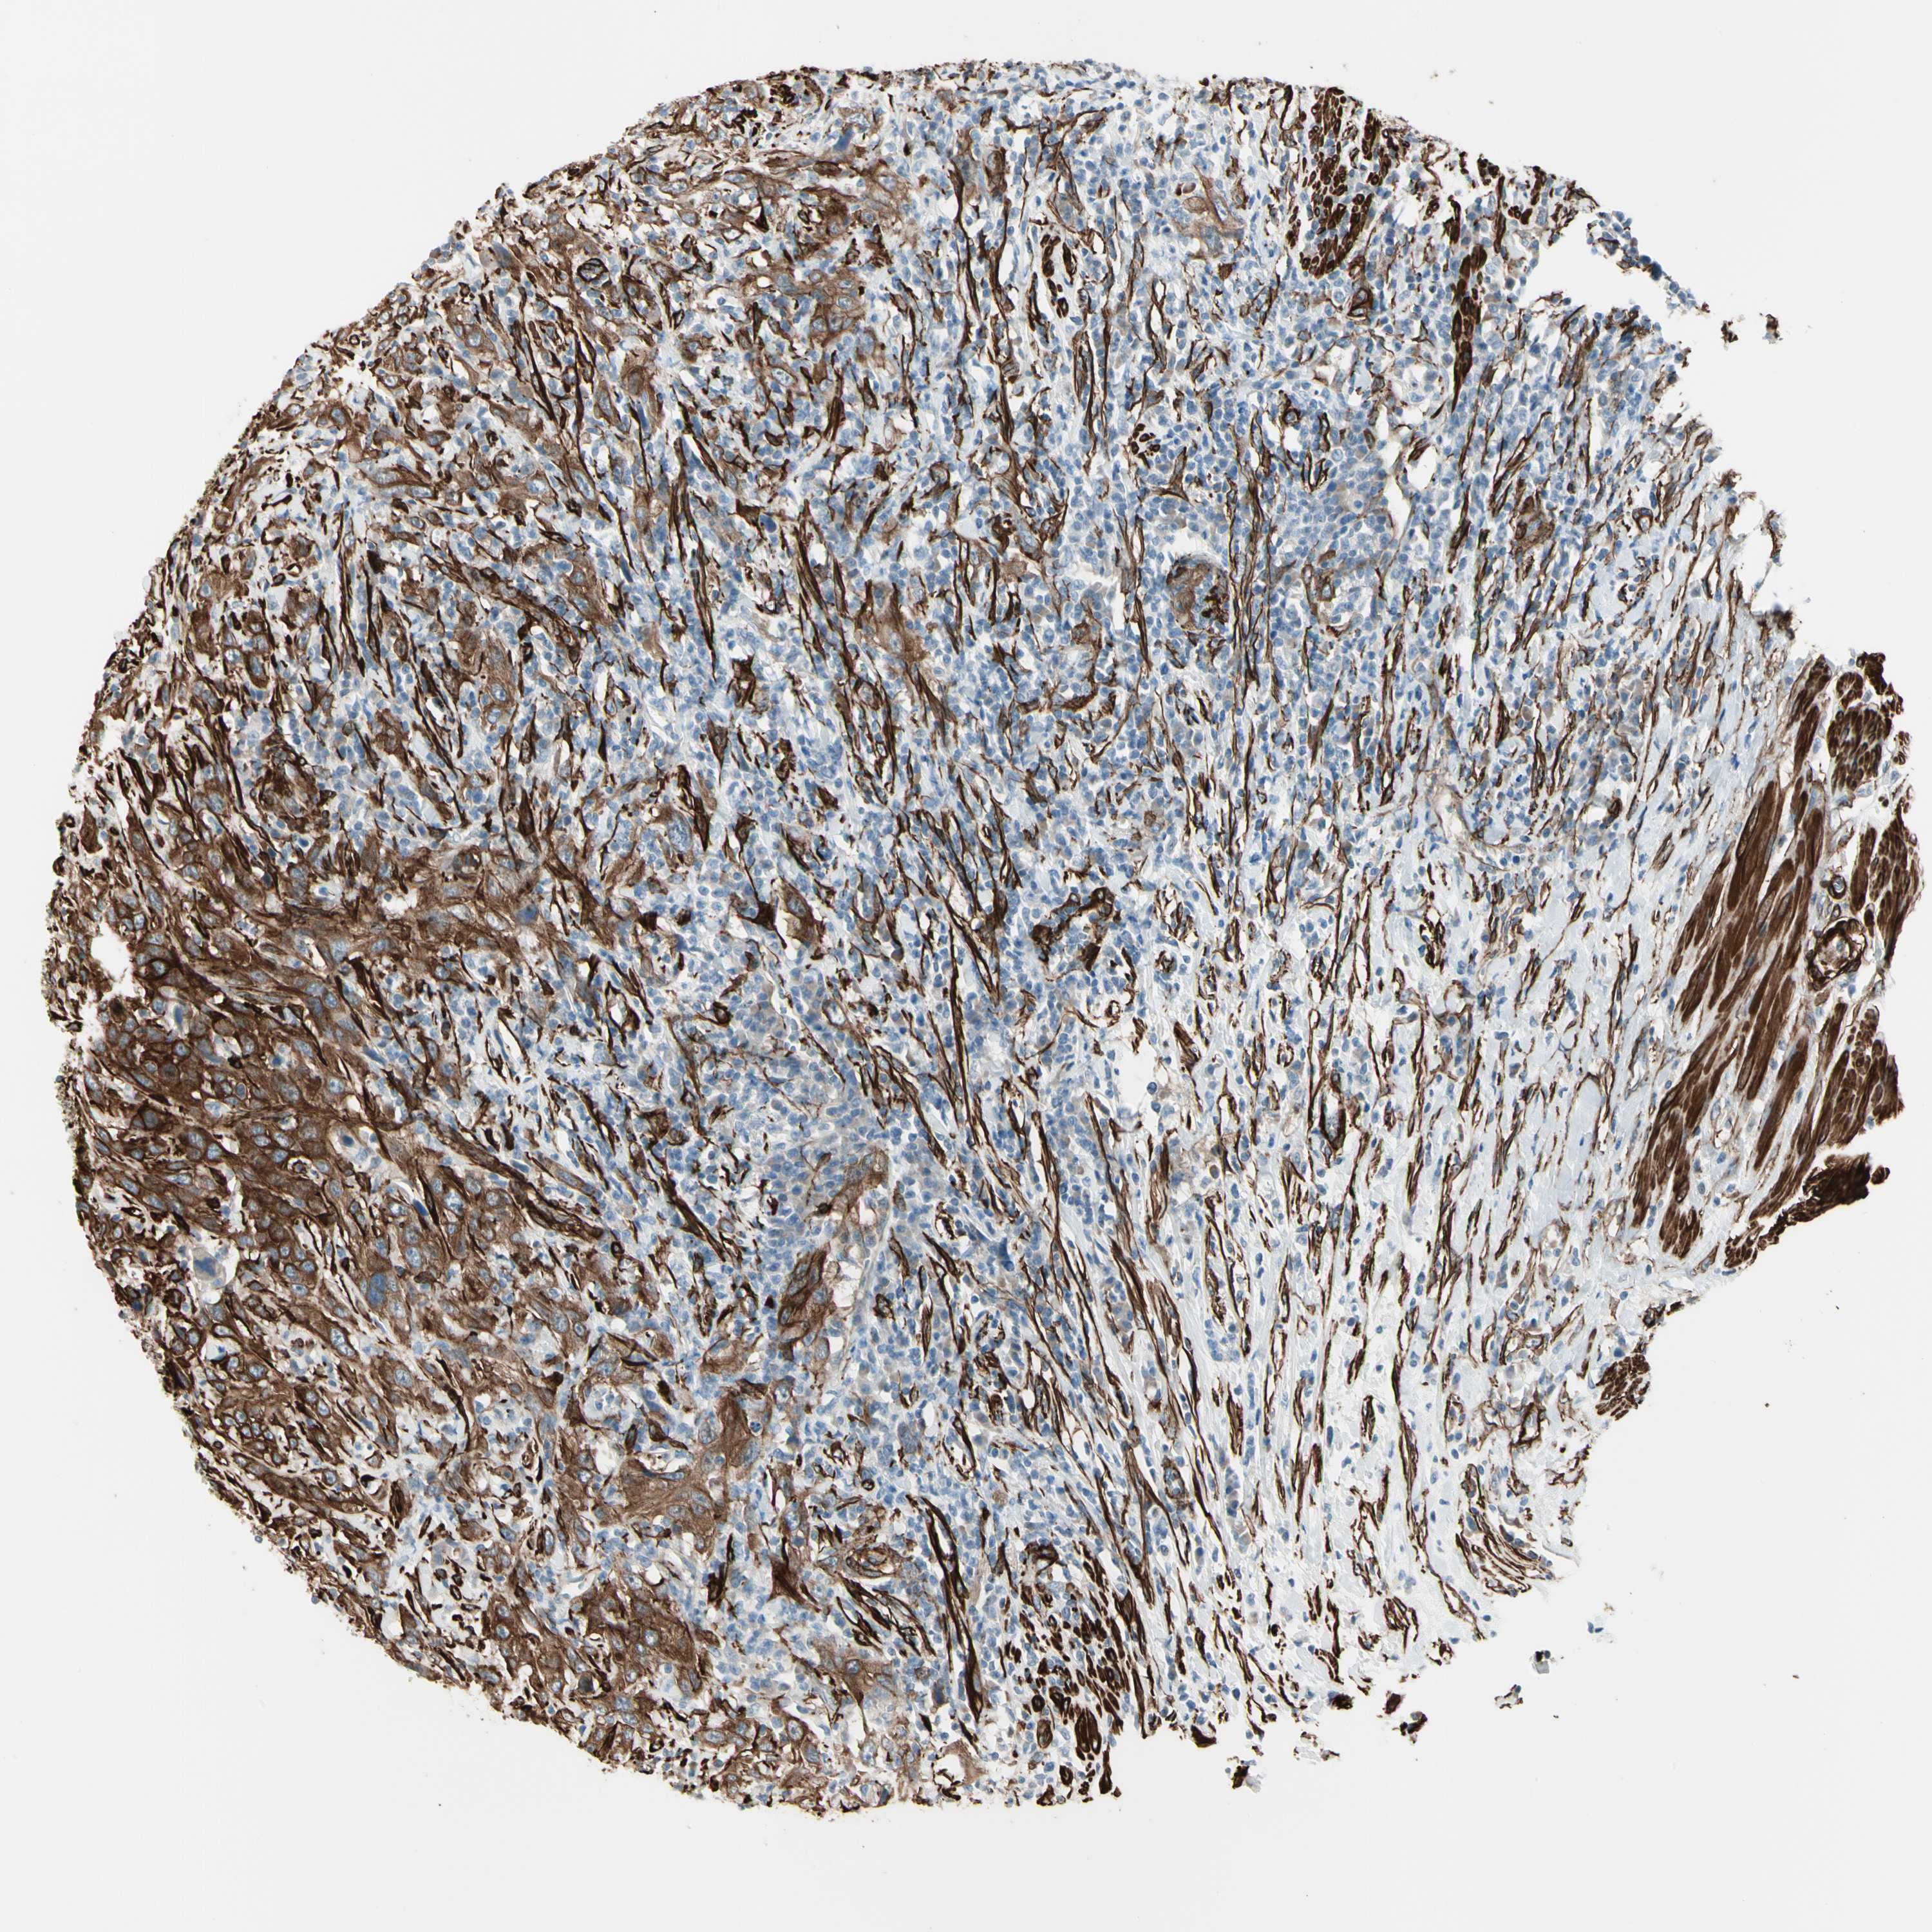

UROTHELIAL CANCER - Protein expressioni

A mouse-over function shows sample information and annotation data. Click on an image to view it in a full screen mode. Samples can be filtered based on level of antibody staining by selecting one or several of the following categories: high, medium, low and not detected. The assay and annotation is described here.

Antibody stainingi

Antibody staining in the annotated cell types in the current human tissue is reported as not detected, low, medium, or high, based on conventional immunohistochemistry profiling in selected tissues. This score is based on the combination of the staining intensity and fraction of stained cells.

Each image is clickable and will lead to virtual microscopy that enables deeper exploration of all samples and also displays staining intensity scores, fraction scores and subcellular localization as well as patient and tissue information for each sample.

Antibody HPA008066

Antibody HPA017330

Antibody CAB000006

Urothelial carcinoma, Low grade

Urothelial carcinoma, High grade